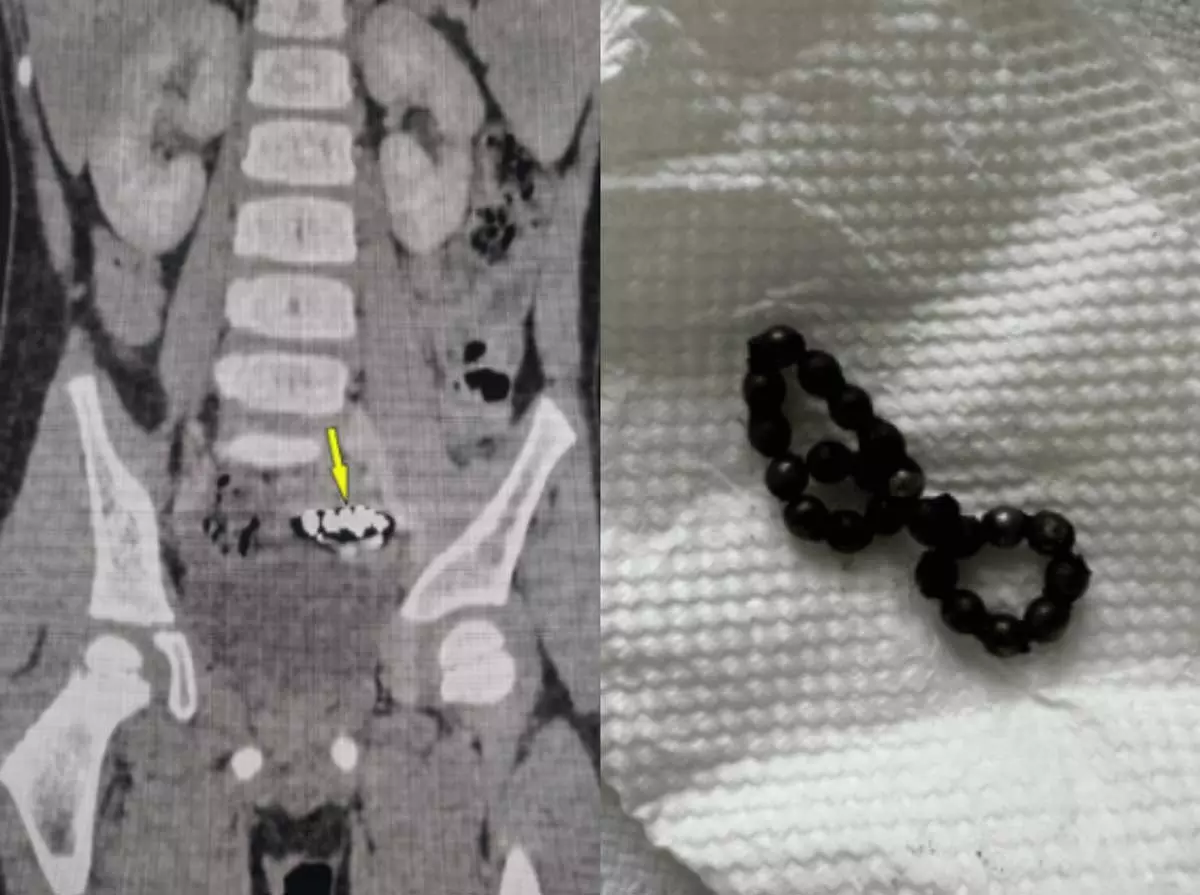

오만 소하르 병원 소아과 의료진에 따르면, 4세 남아가 1년간 지속적인 복통을 겪었다. 초기에는 단순 변비로 판단돼 관련 치료를 받았지만, 증상이 호전되지 않았다. 이에 추가로 엑스레이 검사를 받았다. 그 결과, 하복부에 동글한 이물질이 여러 개 붙어 있는 것을 확인했다.

이에 의료진은 복강경 수술을 진행했다. 배에 작은 구멍을 낸 후 카메라와 수술 도구를 넣는 수술로, 출혈이나 흉터가 상대적으로 적다. 스물두 개의 자석이 발견됐고, 서로 붙어 있는 상태였다. 이로 인해 장 일부가 괴사돼 소장 일부를 절제했다.